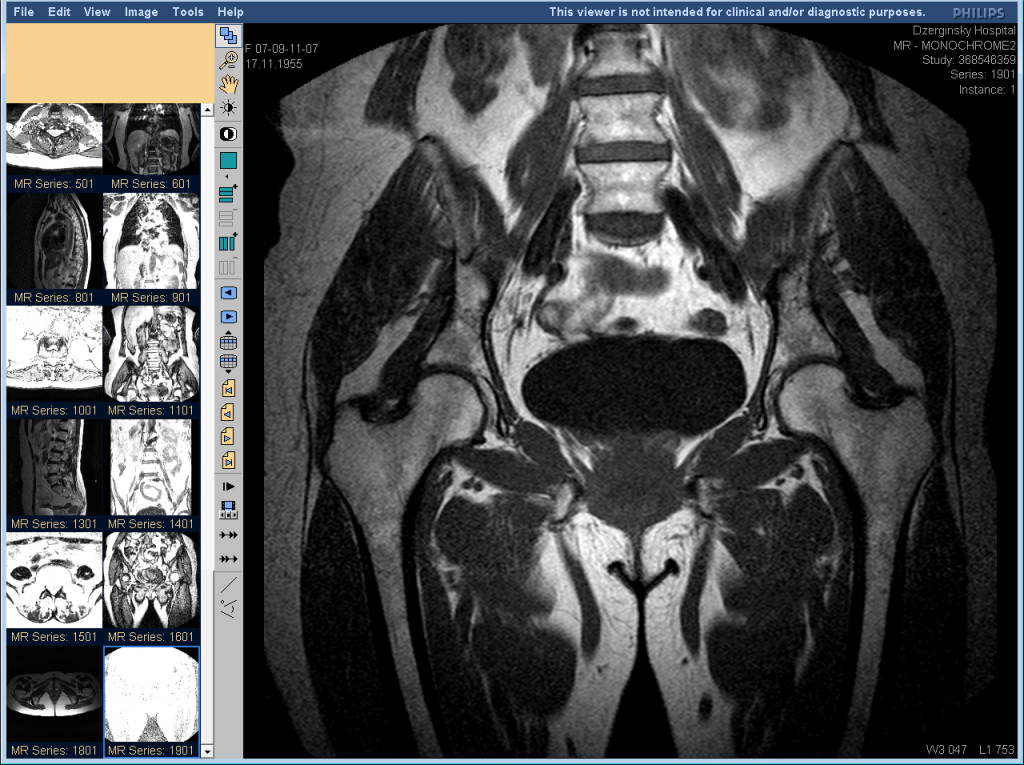

Врачи отмечают, что МРТ тазобедренного сустава является важным инструментом для диагностики различных заболеваний и травм. С помощью магнитно-резонансной томографии можно получить детализированные изображения мягких тканей, хрящей, связок и суставной капсулы. Это позволяет выявить такие патологии, как артрит, бурсит, разрывы связок и повреждения менисков. Специалисты подчеркивают, что МРТ особенно полезна для диагностики скрытых травм, которые могут не проявляться на рентгеновских снимках. Кроме того, исследование помогает оценить состояние суставного хряща и выявить признаки дегенеративных изменений, что имеет важное значение для выбора правильной тактики лечения. Врачи рекомендуют проводить МРТ при наличии болей в тазобедренном суставе, ограничении движений или после травм для более точной диагностики и эффективного лечения.

В работе сустава задействовано много элементов: связки, сухожилия, мышцы, кости, суставная сумка и находящаяся в ней жидкость, кровеносные сосуды. Томография тазобедренного сустава показывает каждый элемент сустава в поперечных и косых плоскостях.

Во время хода процедуры слышится постукивание – это происходит из-за работы томографа. Пациент не чувствует никаких болевых ощущений и после МРТ не нужно даже отдыха, можно сразу же возвращаться к обычной жизни. На видео и фото можно увидеть, как делают МРТ, и как выглядят результаты.